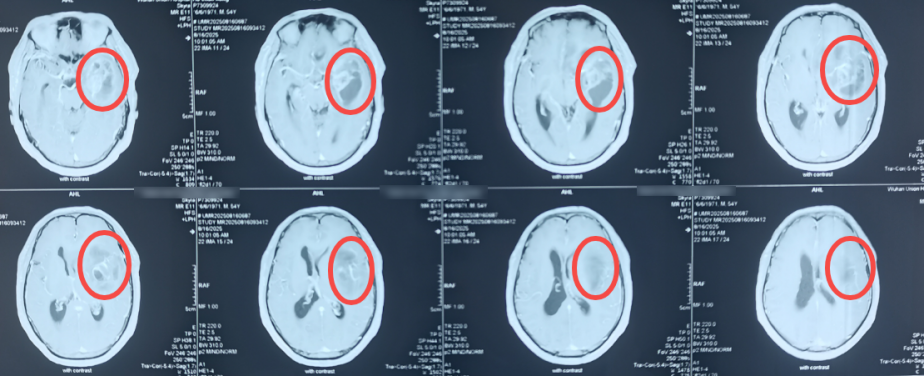

术前头颅核磁增强(圆圈表示颅内肿瘤占位)

术前脑血管造影(圆圈表示动脉瘤)